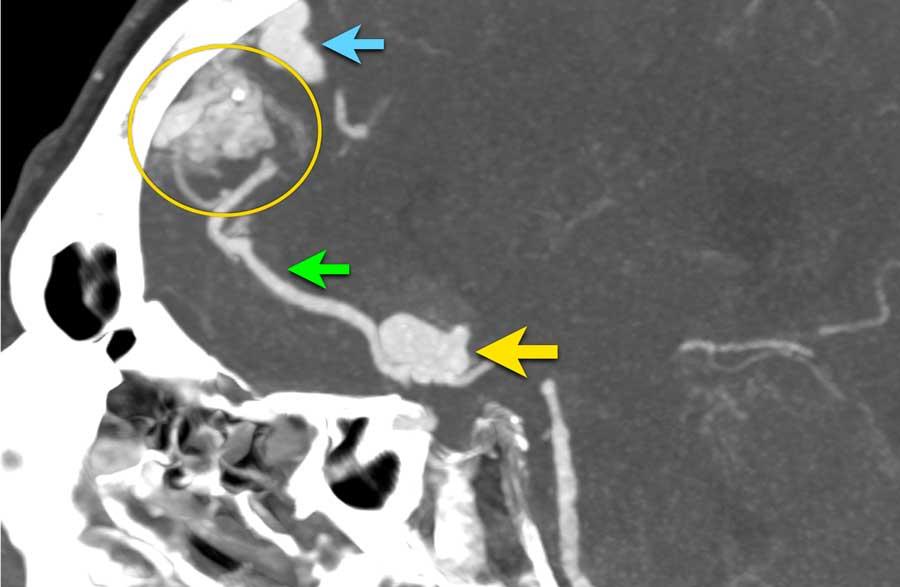

Bệnh nhân nam 65 tuổi với triệu chứng đau đầu khởi phát đột ngột.

NCCT cho thấy xuất huyết dưới nhện hai bên và xuất huyết nhu mô não (mũi tên vàng).

CTA cho thấy tại vị trí xuất huyết nhu mô có một túi phình liên quan đến dòng chảy của động mạch thông trước, được xem là nguyên nhân gây xuất huyết dưới nhện.

Lưu ý khối xuất huyết bên cạnh túi phình (vòng tròn).

CTA cũng cho thấy một AVM với nidus ở thùy trán trái (mũi tên xanh lá).

Ở bệnh nhân có AVM, huyết động học có thể thay đổi theo cách làm suy yếu thành động mạch và dẫn đến hình thành túi phình.

Hình CTA nhìn nghiêng:

- Túi phình liên quan đến dòng chảy kèm túi phình con tại đáy túi phình – mũi tên vàng

- Động mạch nuôi – mũi tên xanh lá

- Nidus AVM – vòng tròn

- Tĩnh mạch dẫn lưu giãn – mũi tên xanh dương